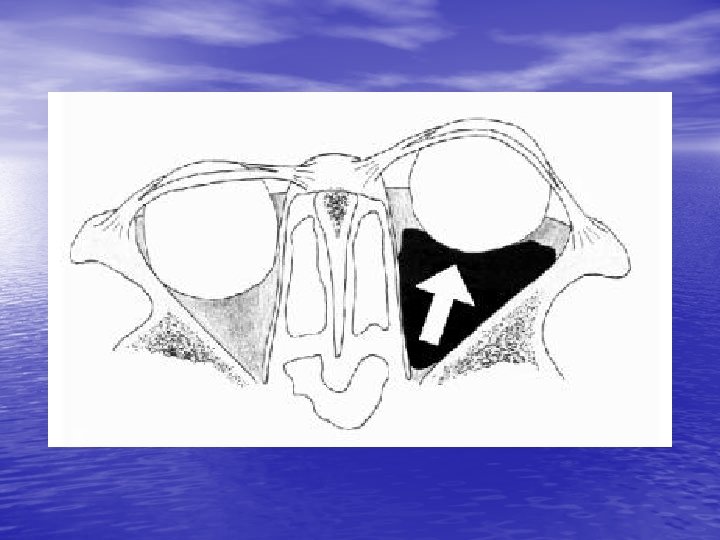

Retrobulbar Hemmorhage: • Hemmorhage in potential space surrounding • • globe may increase intraorbital pressure and cause CRAO. Symptoms=proptosis, visual loss, increased IOP Signs= CRAO Dx= above + orbital CT scan Tx=immediate optho consult, IV mannitol +/lateral canthotomy or anterior chamber paracentesis